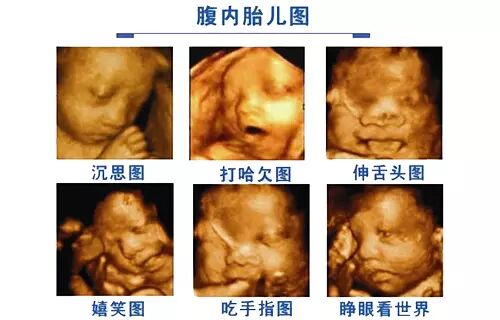

胎儿四维超声检查技术,也就是四维成像技术,是目前先进的超声诊断技术,能直观、立体显示人体器官的三维结构及动态、实时地观察立体结构,筛查发育情况,广泛运用于对胎儿进行超声检查。在立体观察宫内胎儿发育情况的同时,还能清晰显示胎儿在宫内的动态。

• 查看胎儿的活动:可以检查到胎儿在宫内是否缺氧,肢体运动、胎儿的吞咽动作等,能够看到胎儿在母体内的活动状况。